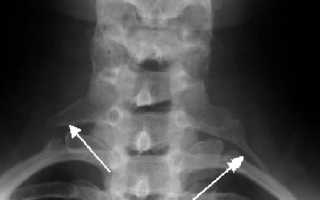

Шейные ребра